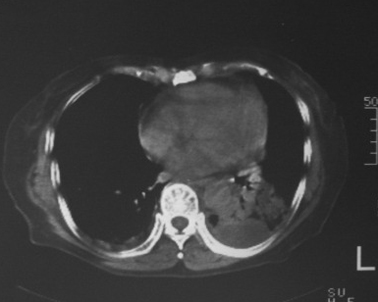

女,80岁,10天前胸片示双下肺感染,正规治疗后复查。体温不高,有脓痰,无臭味。

左肺下叶块影约为17hu!

左下肺片状及块状密度增高影,其内见液化密度影及充气支气管影.考虑炎性病灶,肺脓肿形成

左肺下叶大部实变,内可见含气支气管征。后部见长椭圆形低密度区,周围坏一薄壁。

考虑:左下肺炎症,包裹性胸腔积液。

支持:左肺下叶大部实变,内可见含气支气管征。后部见长椭圆形低密度区,周围环一薄壁,局部胸膜增厚。结合病史考虑:左下肺炎症,包裹性胸腔积液。

左肺下叶炎症并脓肿形成,双侧胸膜炎

左下肺脓肿伴左下胸腔包裹性积液。